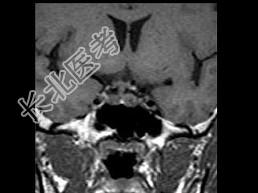

- 单项选择题女,25岁, 双侧泌乳,月经不调半年, 服药效果不佳,根据所提供图像, 最可能的诊断是 ( )

E、垂体微腺瘤